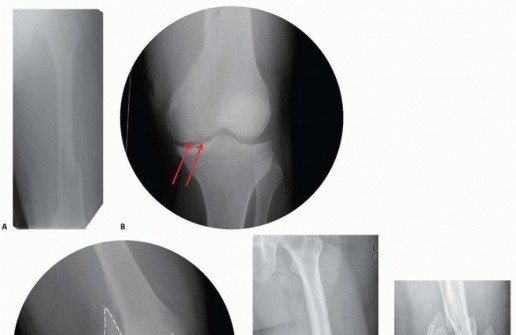

### FIG 6 • A. Axial CT image of patient in FIG 5A-C confirming the type B3 fracture of the medial femoral condyle. B. Axial CT image of the patient in FIG 5D-F. C-E. CT images of the patient in FIG 5G,H show the nondisplaced intercondylar split as well as the low lateral fracture line and extensive posterior metaphyseal comminution (type C2).

### FIG 7 • AP (A) and lateral (B) views of a three-dimensional (3-D) CT reconstruction of the patient in FIG 3B with a distal femur fracture. The fracture is well defined. C. An oblique 3-D CT reconstruction view showing the same patient and the rotational malalignment between condyles. ## SURGICAL MANAGEMENT 471 The goal of any treatment, nonoperative or operative, is to maintain or restore the congruity of the articular surface and restore the length and alignment of the femur and, subsequently, the limb. Once surgery is deemed appropriate for the patient and the particular injury, the surgical technique options available are determined by the particular fracture pattern. Distal femur fractures have been classified several ways. The OTA/AO classification is probably the most widely accepted classification system and allows some guidance on which techniques are best ( FIG 8; Table 1). Treatment also must be determined based on factors other than the classification alone. The degree of comminution and injury to both the articular surface and bone The amount of fracture displacement The soft tissue injury Associated injuries, other fractures, and injury to neurovascular structures